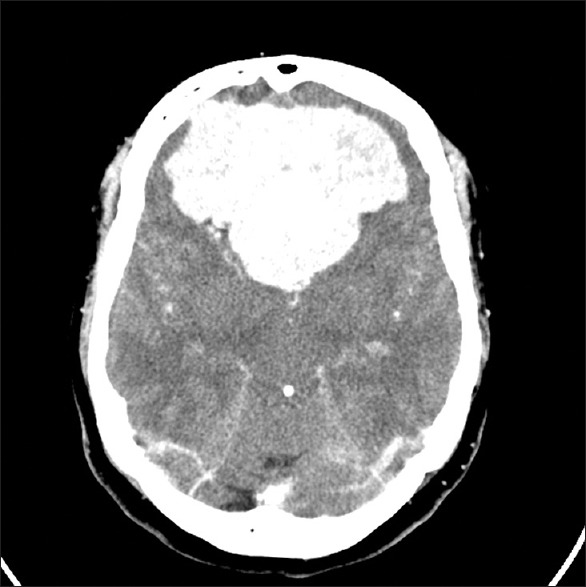

• 脑膜瘤的典型CT表现是什么?脑膜瘤MRI表现有哪些?

脑膜瘤的典型CT表现是什么?脑膜瘤MRI表现有哪些?

2021-08-04 10:48:50

脑膜瘤生长缓慢,常压迫周围组织引起相应的神经症状和体征,造成不同的障碍与肿瘤部位有关。脑膜瘤的典型CT表现是什么?脑膜瘤MRI表现有哪些?...